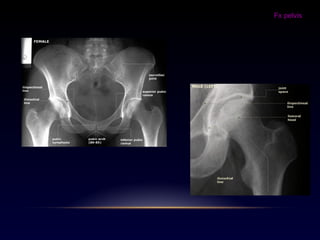

-Fx cadera

Fx cadera